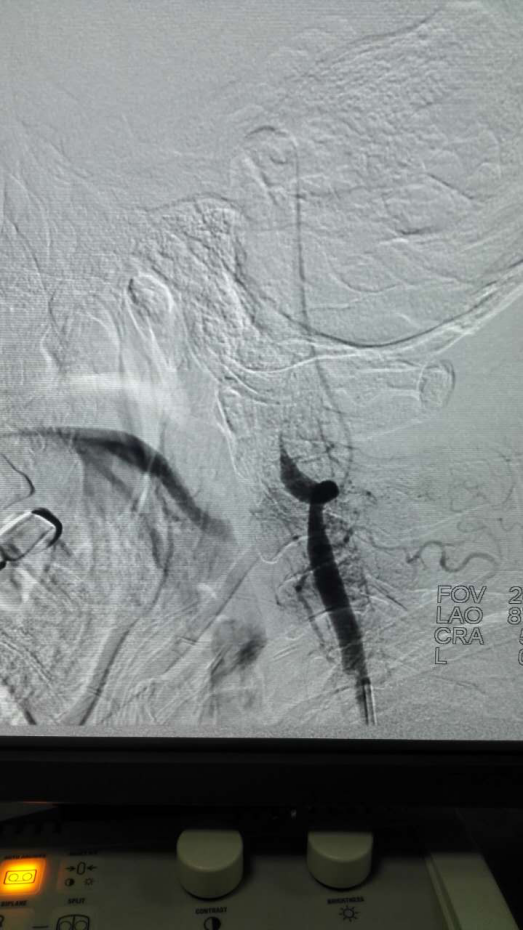

2、以下两图为术中DSA造影证实基底动脉及左侧椎动脉闭塞

3、以下两图为术后DSA造影证实基底动脉及左侧椎动脉开通良好